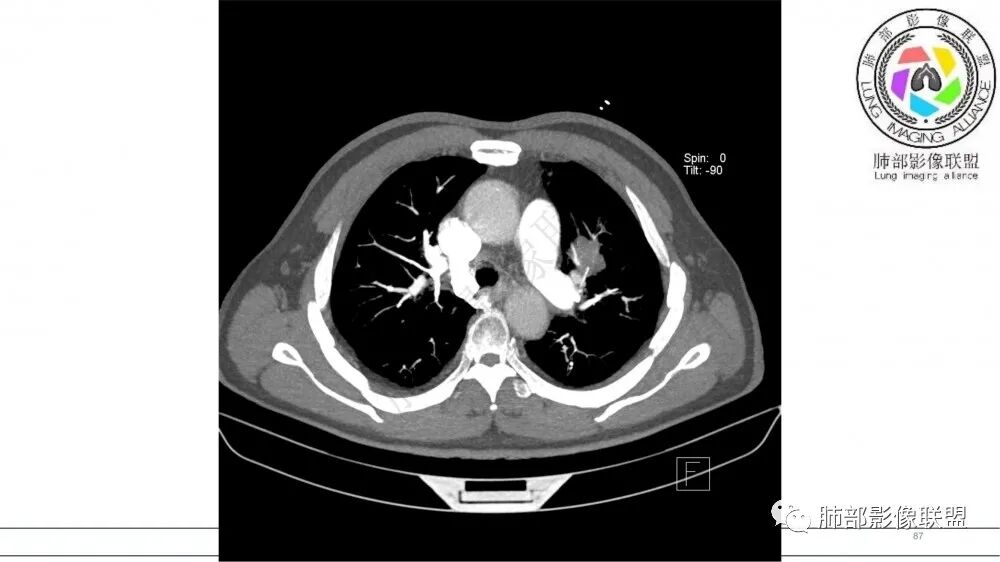

左肺上叶前段支气管内铸形生长软组织影,增强后均匀强化,远侧见斑片状磨玻璃影。考虑恶性病变,粘表?粘液腺?

老年男性,左肺上叶前段支气管内铸形阴影,增强后病灶不均匀强化,内部有坏死?远端可见斑片状阴影(阻塞性肺炎)。考虑恶性病变,老年人,鳞?类癌?粘表不能排除。

老年男性,肺气肿,吸烟史,左肺上支气管腔内铸型高密度影,呈指套状,远端多发树芽,增强不均匀强化,考虑鳞癌,鉴别小细胞癌

B3指套征,常规不是鳞癌就是ABPA,有强化丶血管造影征,倾向于鳞癌

进一步查支气管镜,有胸闷,看看嗜酸性粒细胞高不高,查一下曲霉菌特异性ⅠgG丶ⅠgE,总lgE鉴别ABPA

指套征,扩张支气管内软组织强化,远侧肺野阻塞性炎,纵隔、左肺门肿大淋巴结;老年男性,吸烟,考虑鳞癌,鉴别小

老年男性,术前检查肺气肿背景,左肺上叶结节,沿支气管蠕虫样生长,左肺门及纵隔淋巴结肿大,增强扫描不均匀强化,血管包绕,结合吸烟史,考虑小细胞肺癌。

2021年8月6日晨读病例结果:小细胞肺癌

研究报道,中心型 SCLC 经 CT 扫描后通常支气管表现为鼠尾样狭窄,肺门或纵隔肿块明显,由于肿块沿管壁生长表现为顺延支气管形态的不规则形状。病灶相对特征性影像学表现比如鸭蹼状、腊肠状、葫芦状及葡萄状改变,可以出现血管包埋,很少有空洞、空泡,较少引发肺不张,阻塞性炎症成都较轻。与一般肺癌比较,恶性程度高,侵袭力强、病灶很小就容易远处转移!Herzberg 等[19]研究指出,20%以上 SCLC 倍增时间短,预后不良。